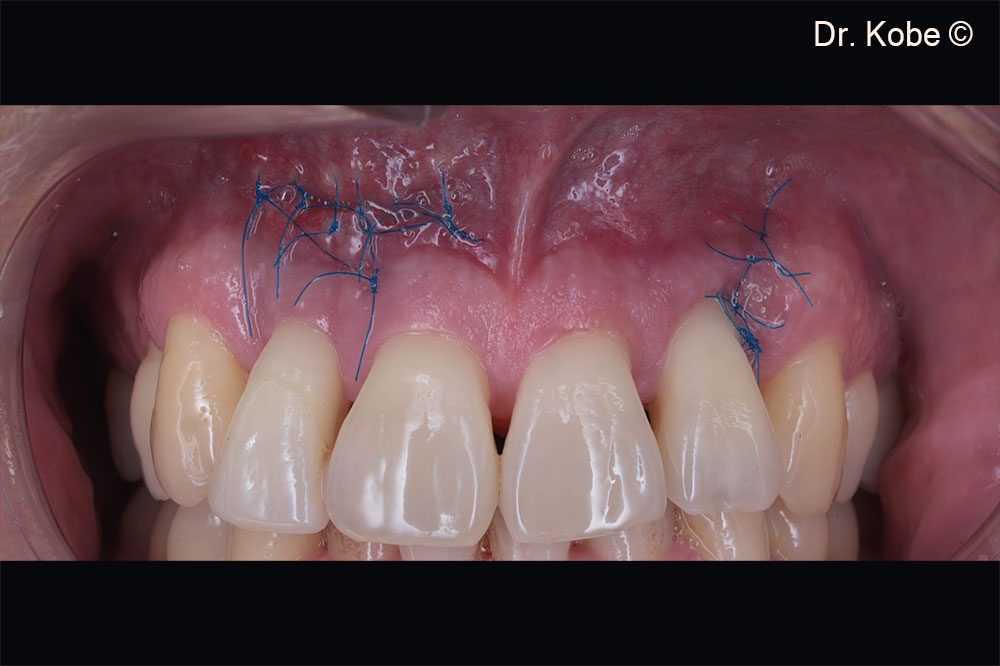

Rạch dọc (EPPT) tại răng liền kề

Khuyết tật được lấp đầy bằng Gen-OS

Vết thương được khâu bằng các mũi khâu gián đoạn